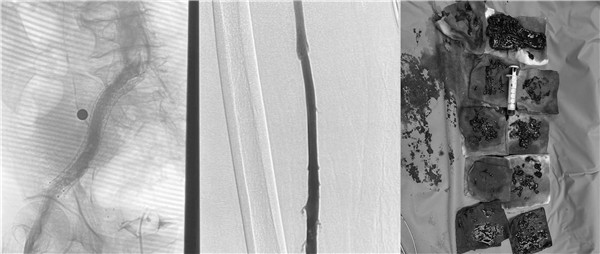

高大爷入院后立刻开启绿色通道,普外科血管介入团队放弃假期休息,当天急诊为他进行了介入手术治疗。为了防止肺栓塞的发生,首先为高大爷进行下腔静脉滤器的植入,与此同时造影显示患者左下肢血管内布满血栓,使用AcoStream血栓抽吸系统为患者清除血管内的血栓,高大爷还存在左侧“髂静脉压迫综合征”立刻完善方案,为他进行球囊扩张,支架植入,在保证患者的安全前提下,采用“一站式”解决方案,一次性为高大爷从病根上解决诱发血栓的原因并治疗了血栓,即刻效果显著,高大爷下肢大腿腿围术前43厘米,术后即刻41.5厘米,术后第一天41厘米,小腿腿围术前34厘米,术后即刻32厘米,术后第一天31厘米。同时也避免可能的PTS发生。介入手术创伤小,仅有一个穿刺点,患者术后恢复快,大大的提高了患者的就医感受,并且为患者节省了费用。

术后